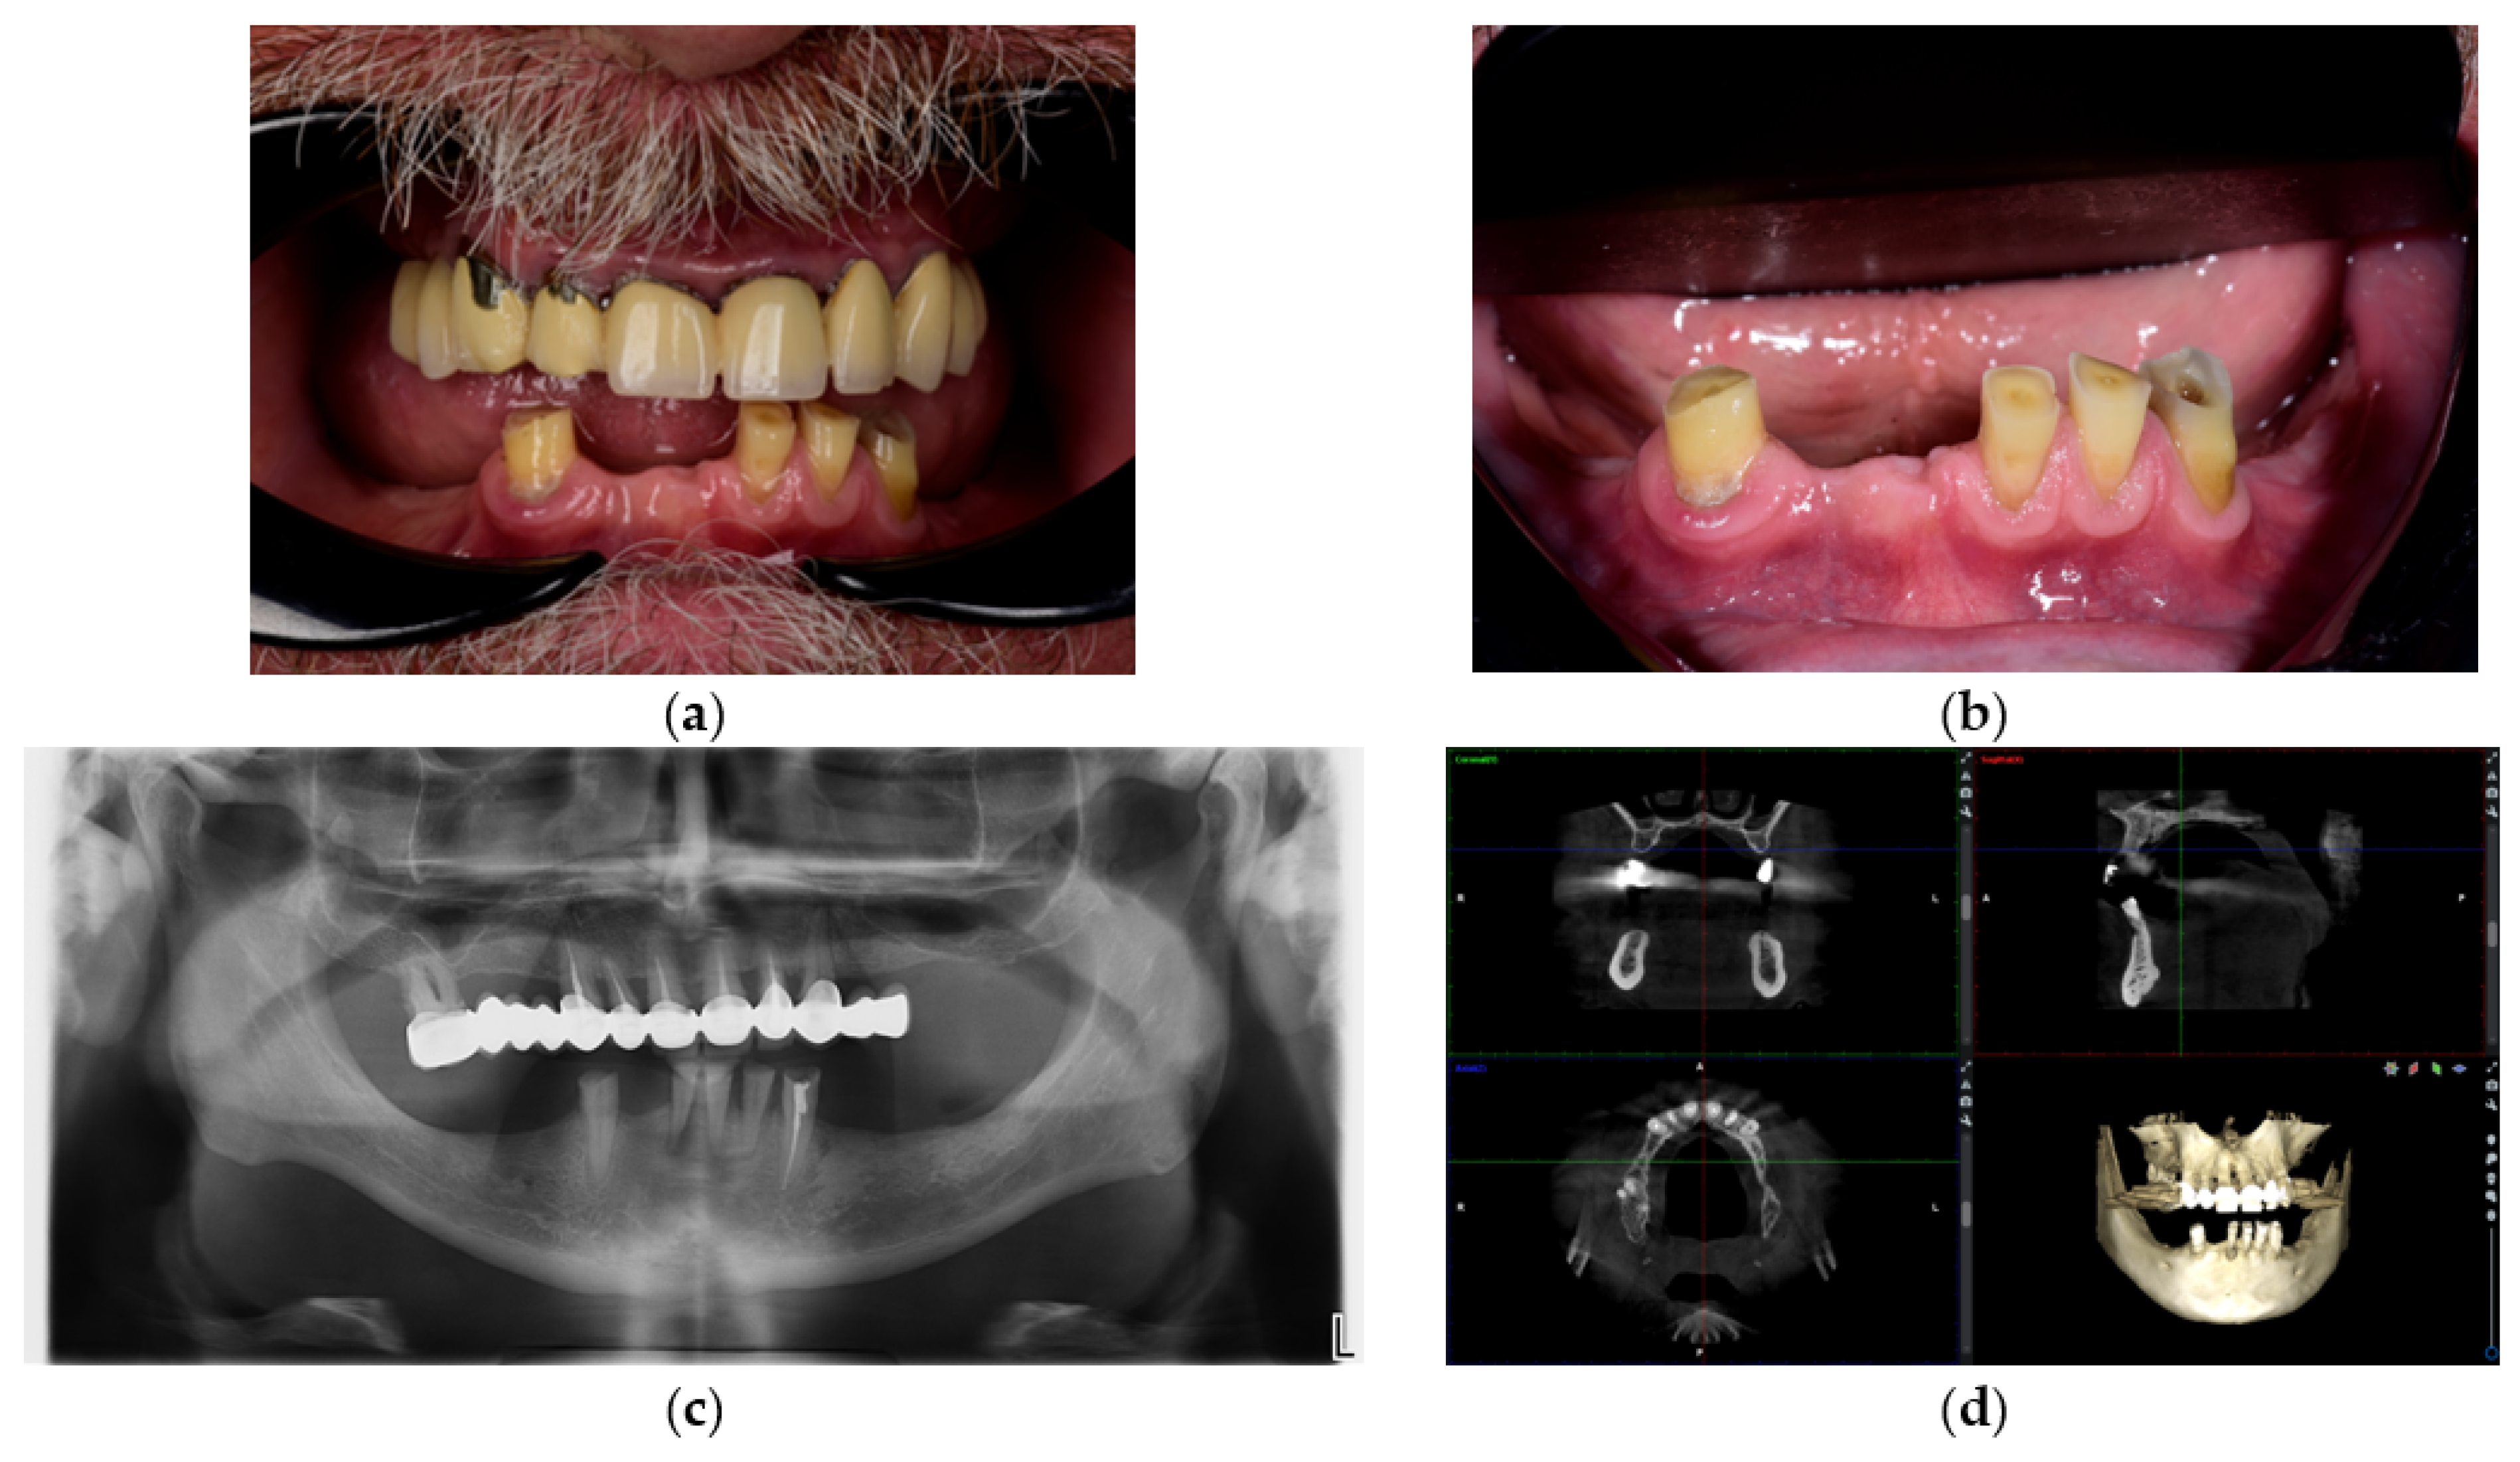

- Prosthetic gingiva adaptation—presence of soft tissue mismatch or loss of adaptation between the prosthetic gingiva and peri-implant soft tissues, documented through standardized frontal and lateral photographs.